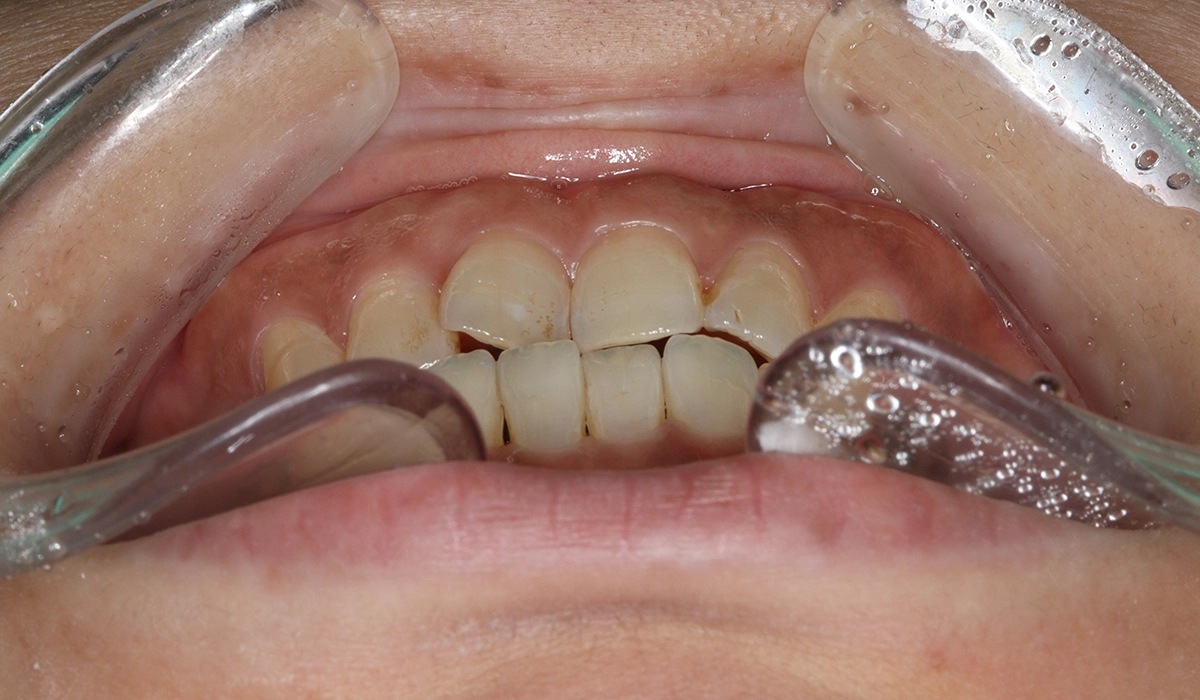

術前:前歯部あおり